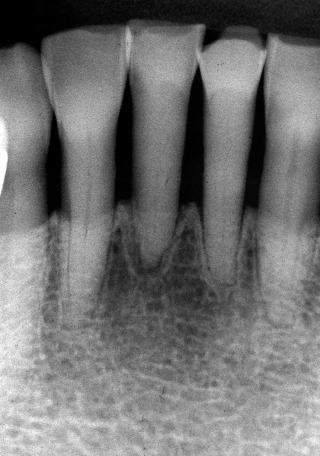

(図5)32年経過(2007年3月5日)、70歳。SPTの重要性とDiathermyの効果

(図4)32年経過(2007年3月5日)、70歳。十分機能している

著者が大学院学生時代からの長い付き合い(33年)の患者である。Sweetが大好物で、脂質異常症と高血圧症があるため、Sugar controlを常々指導するが、なかなか習慣は変えられないようである。長年、編み物教室の教師をしており、現在も毎日出張稽古で飛び回っているようである。ハイヒールをはいて社交ダンスを2〜3時間平気でしたり、毎年海外旅行へ行かれたり、非常に活動的な患者である。一時間かけて大阪から1回/月、定期的にSPTに努めてくれている。

(図3)初診から2年後(1977年7月)、40歳。Splintせずに機能している